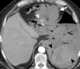

Trauma with gastric perforation

Gastrointestinal perforation, also known as ruptured bowel, is a hole in the wall of part of the gastrointestinal tract. The gastrointestinal tract includes the esophagus, stomach, small intestine, and large intestine. [Source: Wikipedia ]